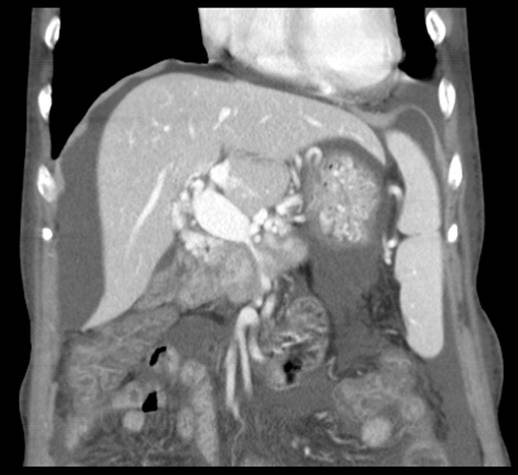

胰腺CT:胰头部病变—性质待查1慢性炎症性?2胰头癌?门静脉局限性狭窄—原因待查炎症所致?肿瘤侵犯?门静脉血栓,下腔静脉局限性狭窄---布-加综合症?大小肠水肿—肠淤血性?胸腹腔大量积液,胆囊缺如—术后改变。

经全科讨论并请普外科、介入科会诊后,考虑慢性胰腺炎所致门静脉狭窄、区域性门脉高压,周围迂曲的侧枝循环导致胆肠吻合口处多发血管扩张并出血。患者转入介入科门静脉造影见门脉远端重度狭窄,用球囊扩张狭窄段,并自肠系膜上静脉及门静脉植入支架。